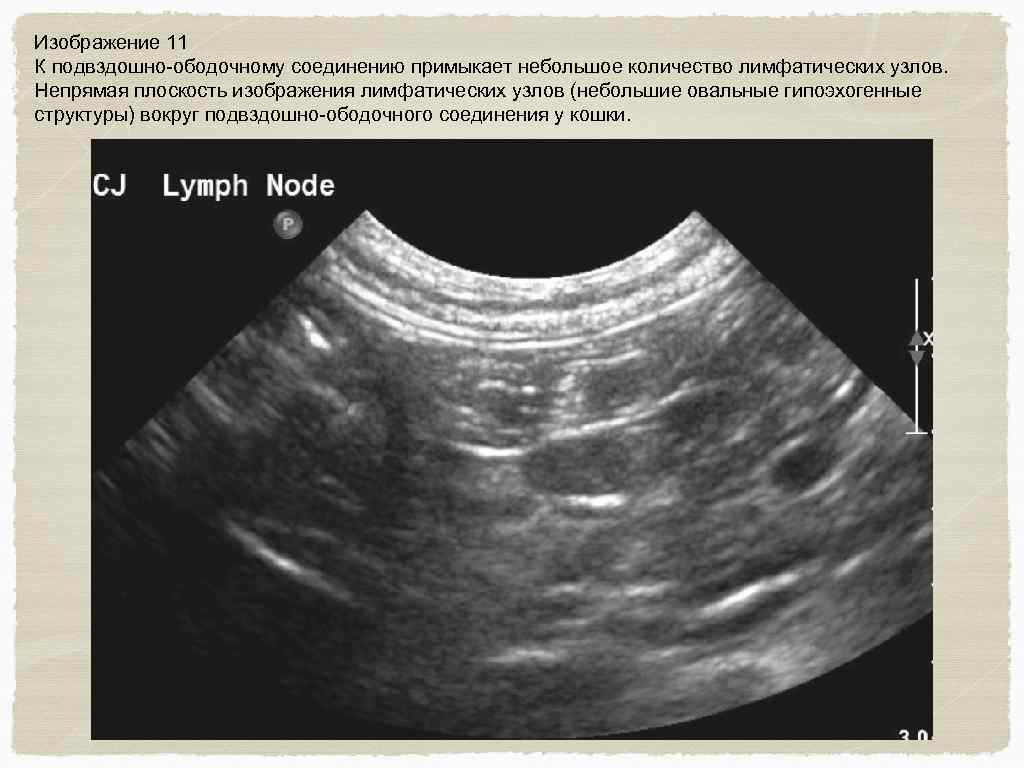

Изображение 11 К подвздошно-ободочному соединению примыкает небольшое количество лимфатических узлов. Непрямая плоскость изображения лимфатических узлов (небольшие овальные гипоэхогенные структуры) вокруг подвздошно-ободочного соединения у кошки.